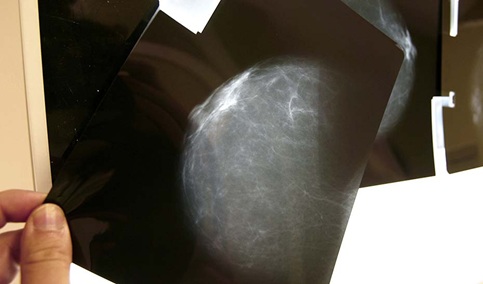

Actualmente, cuando se realiza una mamografía a una mujer dentro del programa de cribado del cáncer de mama existen tres posibles diagnósticos: negativo, positivo y lesión posiblemente benigna.

En el caso de diagnósticos negativos, las pacientes son informadas del resultado; en el caso de diagnósticos positivos, las mujeres son igualmente informadas y derivadas para nuevos procedimientos pero, en los casos en los que se detectan lesiones posiblemente benignas las mujeres pueden no haber sido informadas de que su caso sigue un procedimiento clínico con supervisión médica.

La consejera ha explicado que, en estos casos, hasta tres radiólogos analizan las imágenes y, en función de los factores de riesgo de cada paciente, deciden el tiempo que ha de transcurrir para la segunda prueba. Las pacientes, que viven ajenas a estas circunstancias, reciben al cabo de meses o de un año una llamada que no esperan para esa segunda cita -fijada por el radiólogo- y sienten alarma, intranquilidad y angustia.